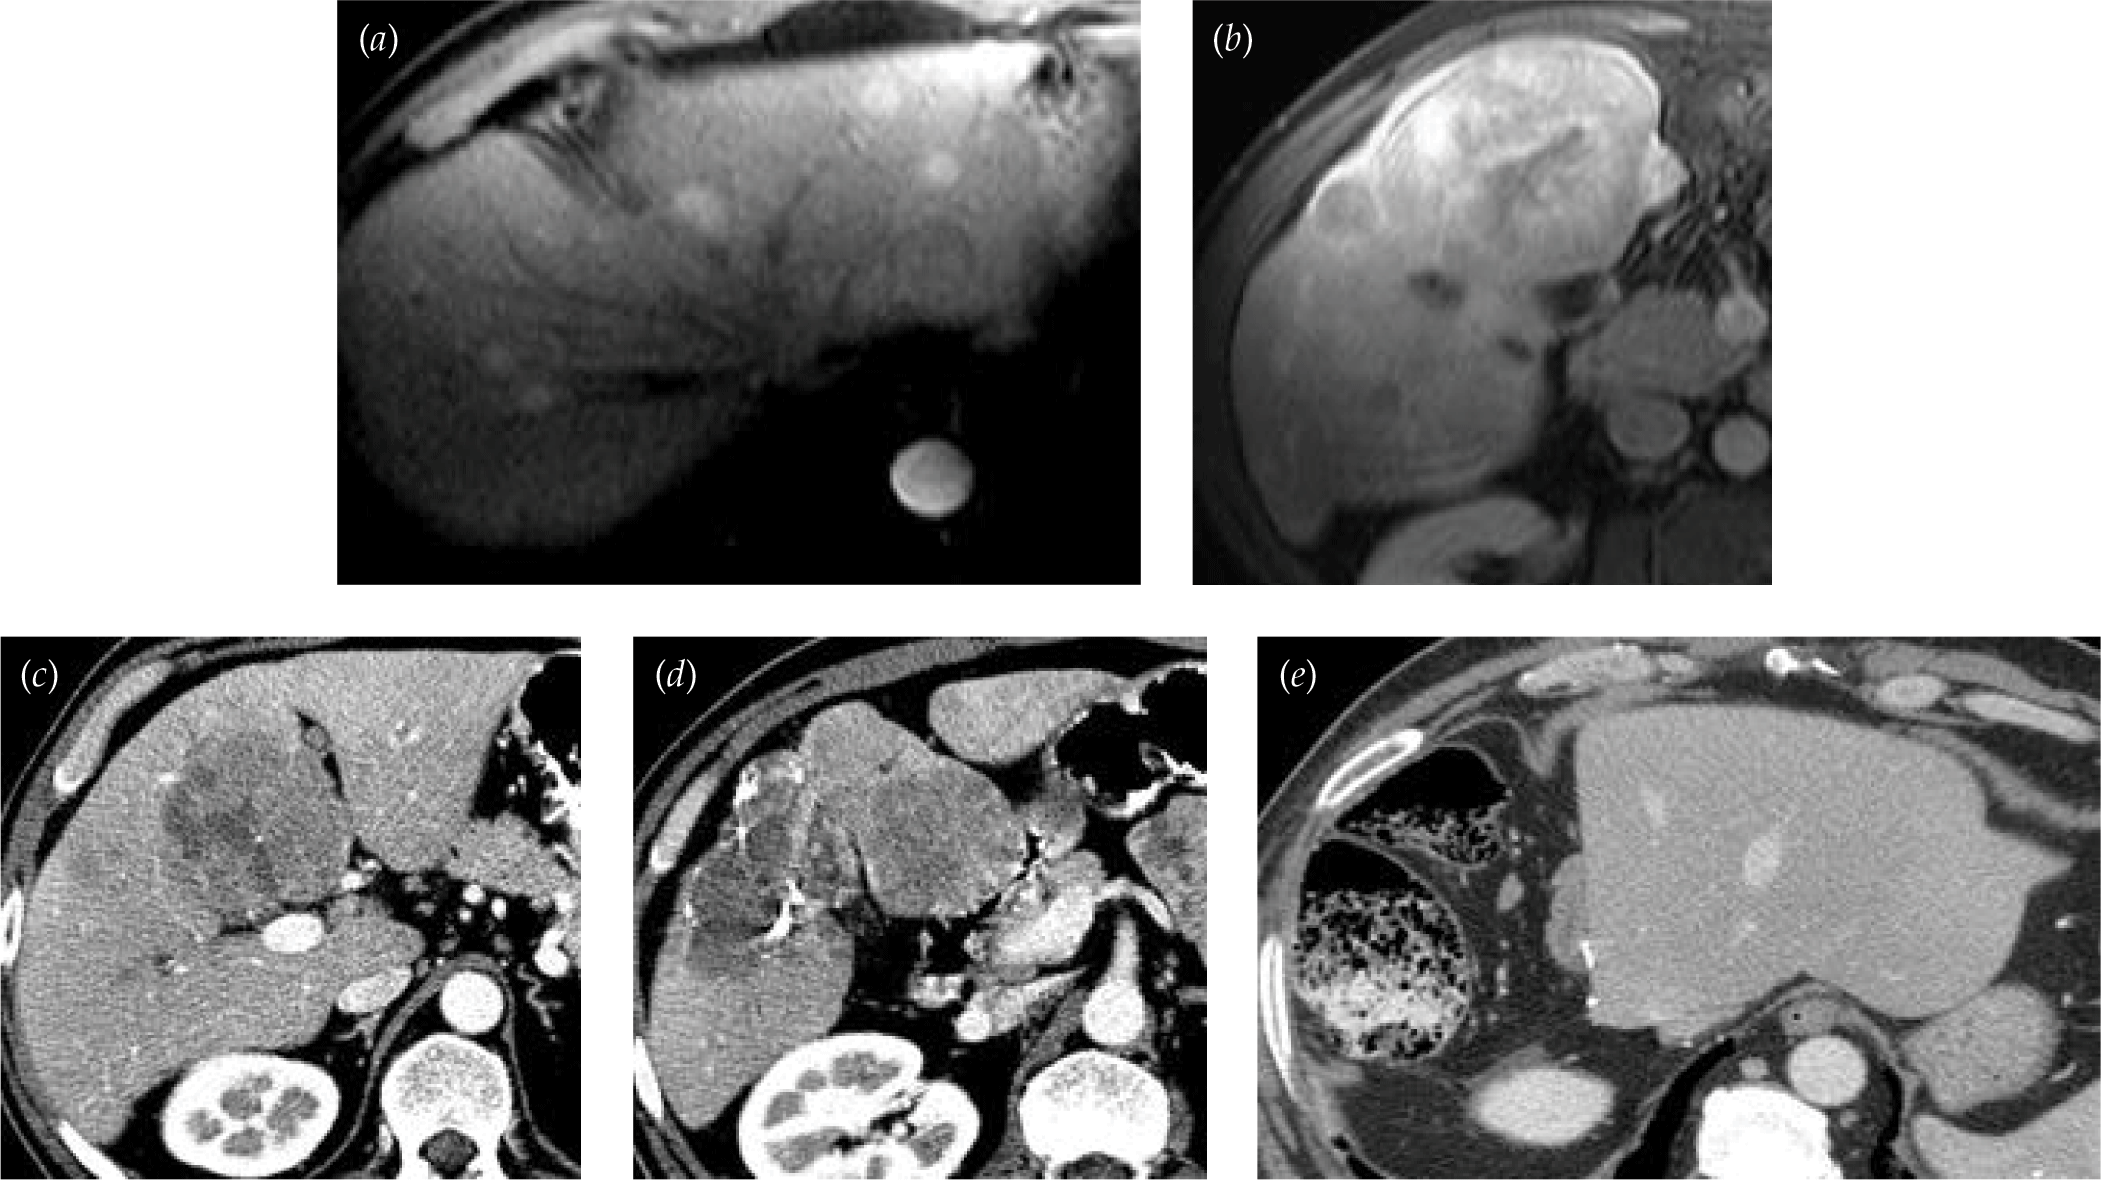

Surgical Treatment for Hepatocellular Carcinoma in the Era of Multiple Staging and Algorithm

- BCLC as the most widely accepted clinical staging system, recent update of the AJCC/UICC staging, AJCC/UICC staging system to predict outcome following surgical treatment